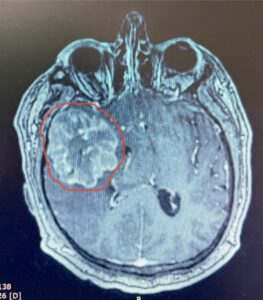

— МРТ-да ми ісігі анықталды. Үш күннен соң, ота жасалды. Біз 6,5-6-6 см болатын обырды алып тастадық. Операция 5 сағатқа созылды. Екі күндесін науқас аяққа нық тұра алды. Қазір өздігінен жүреді, сөйлейді, — деді Балхар Шатуев.